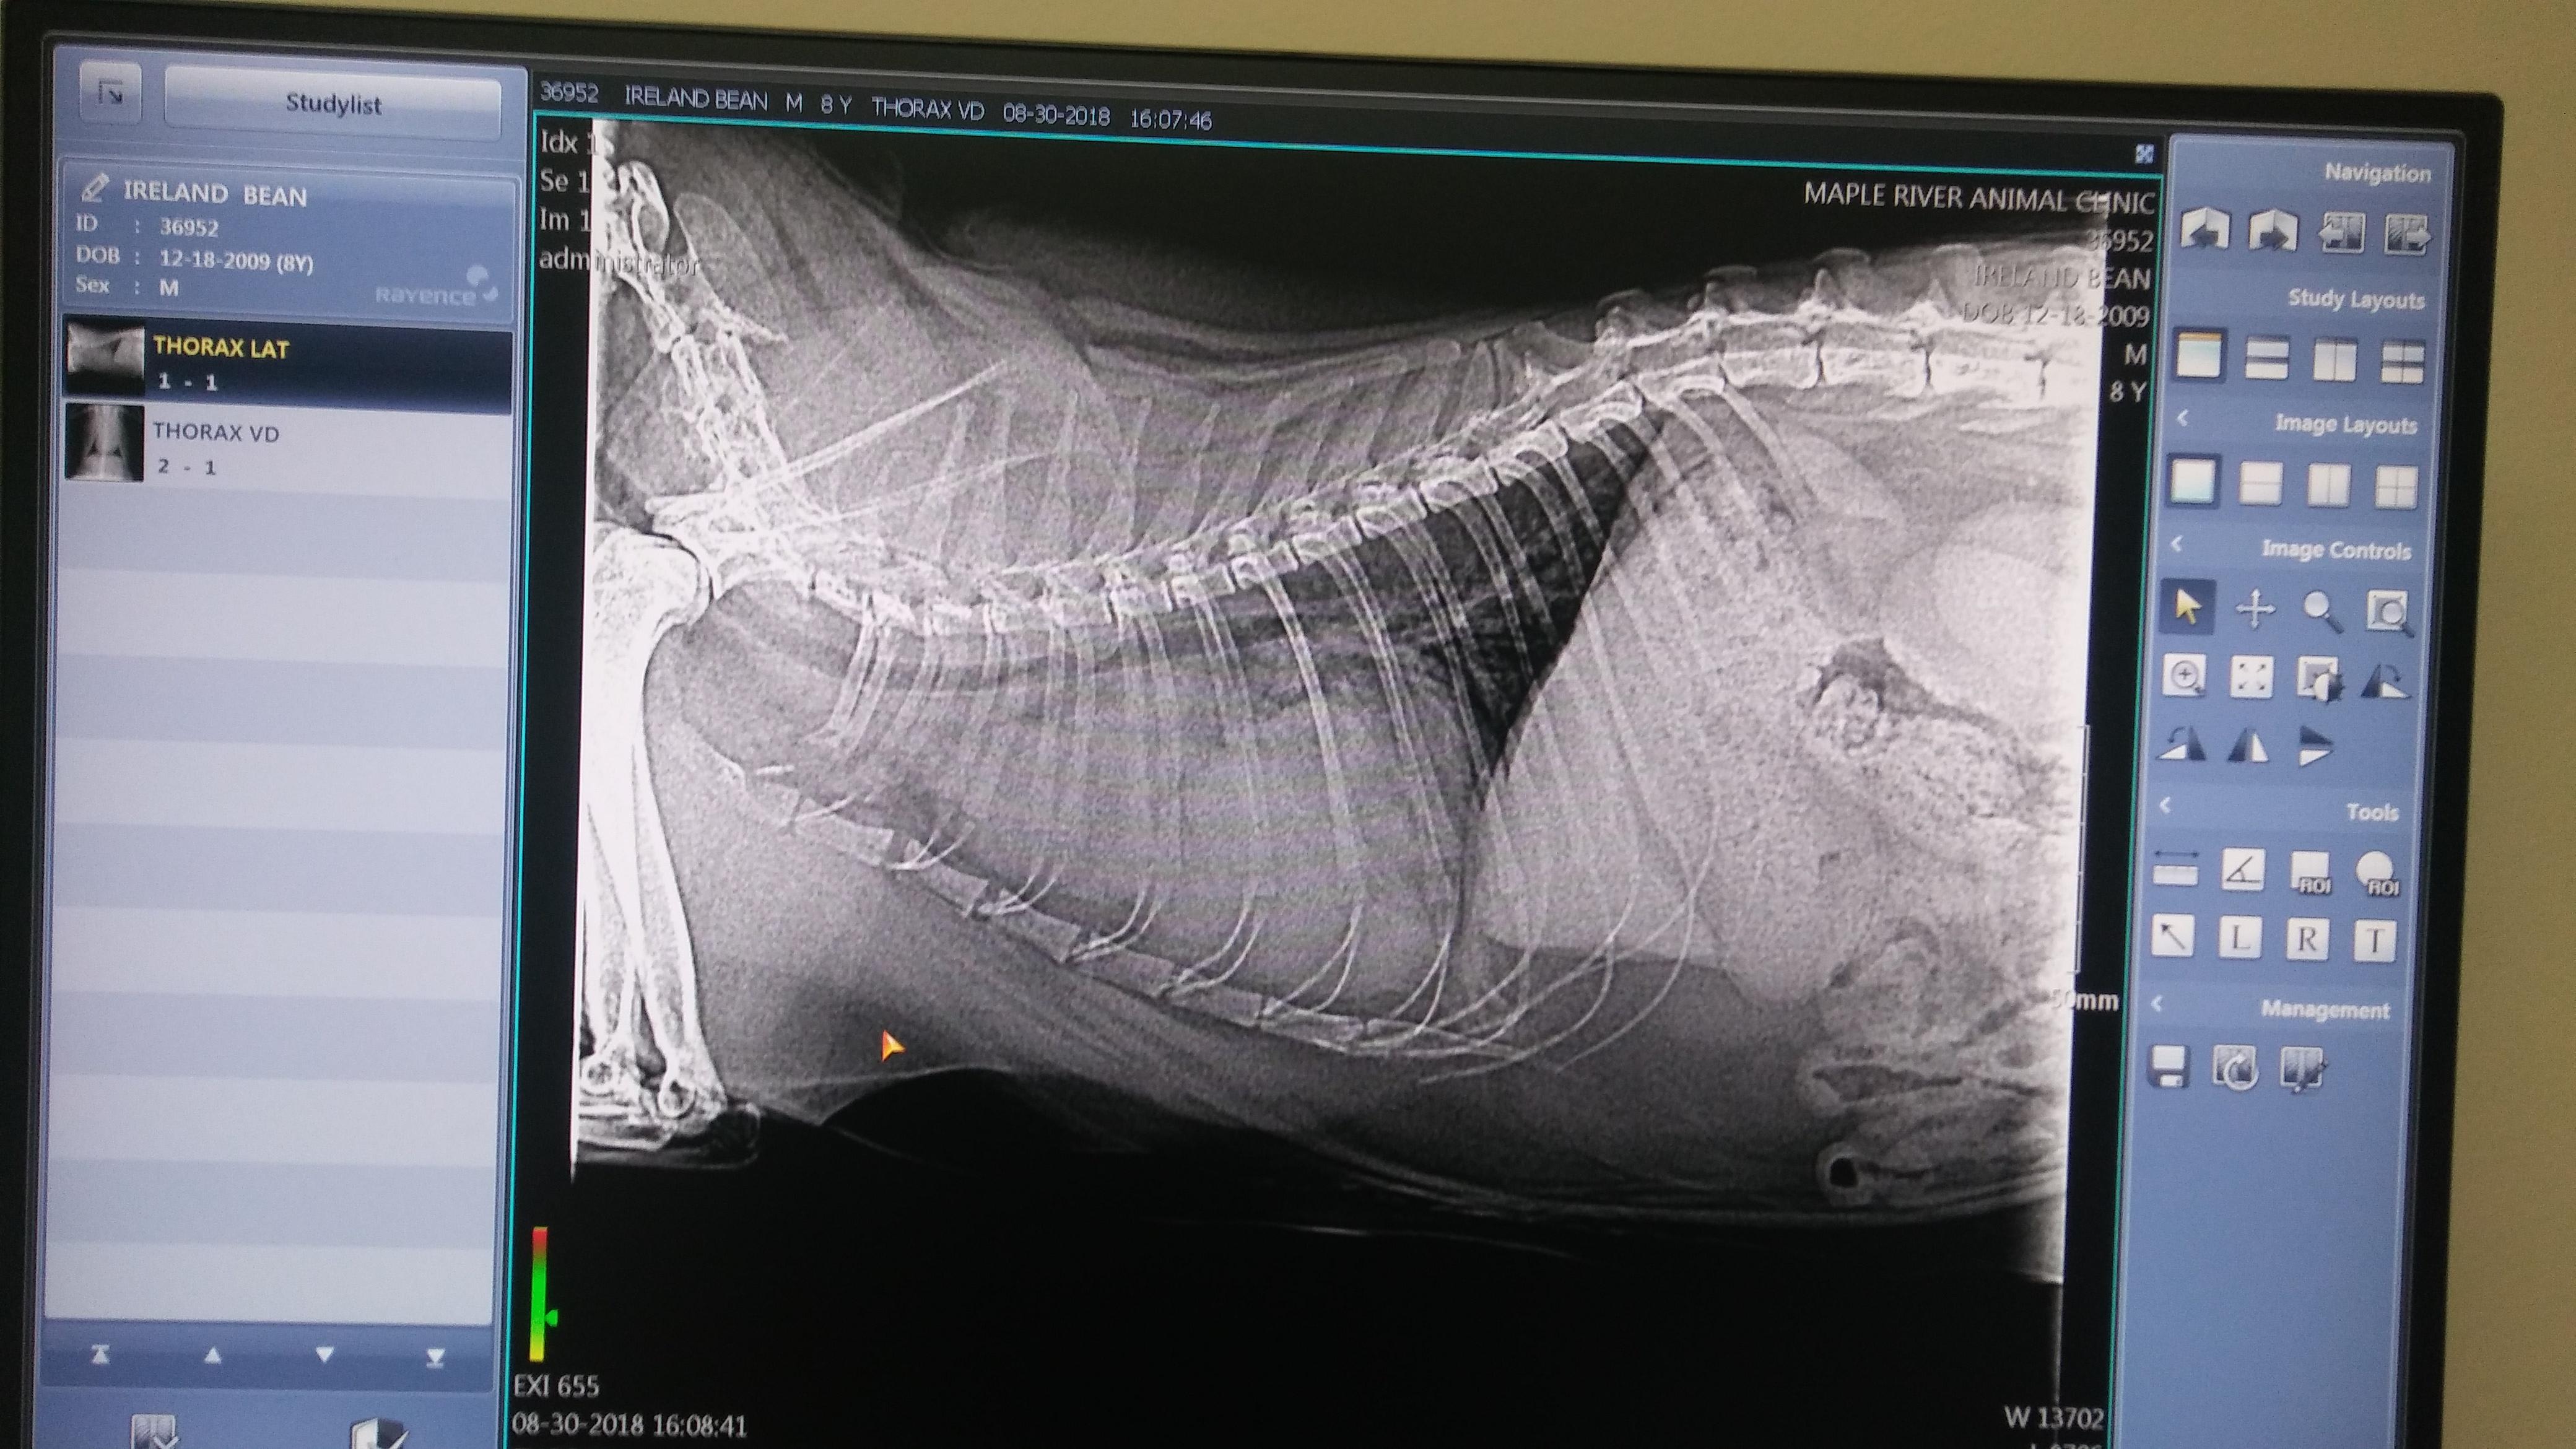

My cat has a very large mass between his chest and the vet doesnt know what it is do you have any idea what it may be

Oh dear! I'm sorry to hear that Bean is having this problem. Unfortunately, there is no way to diagnose what the mass is just by looking at it - he would need to have a biopsy or a fine needle aspirate (FNA) to get a sample of the tissue in the mass for analysis in order to get a specific diagnosis. In general, I can tell you that lymphoma is a common cause of a mass in this area in cats, but there's no way to know for sure if this is what Bean has without further work-up. For a mass or tumor in this area, I would normally recommend referral to a specialist for advanced imaging studies, biopsy or FNA, and discussion of treatment options. Your regular veterinarian should be able to help you set this up, if you wish.